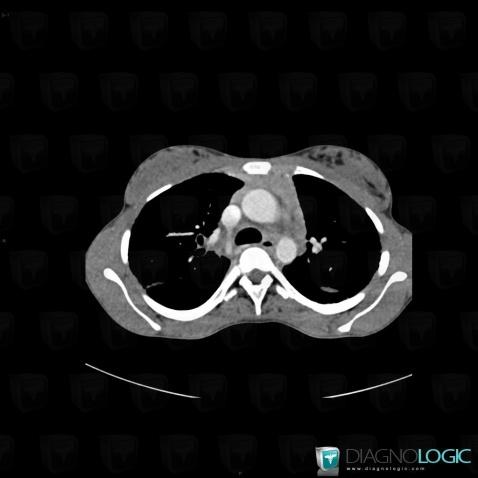

Sarcoïdose, Médiastin, Scanner

Voici les informations spécifiques à l'image clé ci dessus:

- Diagnostic Sarcoïdose, Localisation(s) Médiastin, comportant les gammes Masse médiastinale supérieure

- Diagnostic Sarcoïdose, Localisation(s) Médiastin, comportant les gammes Masse médiastinale antérieure